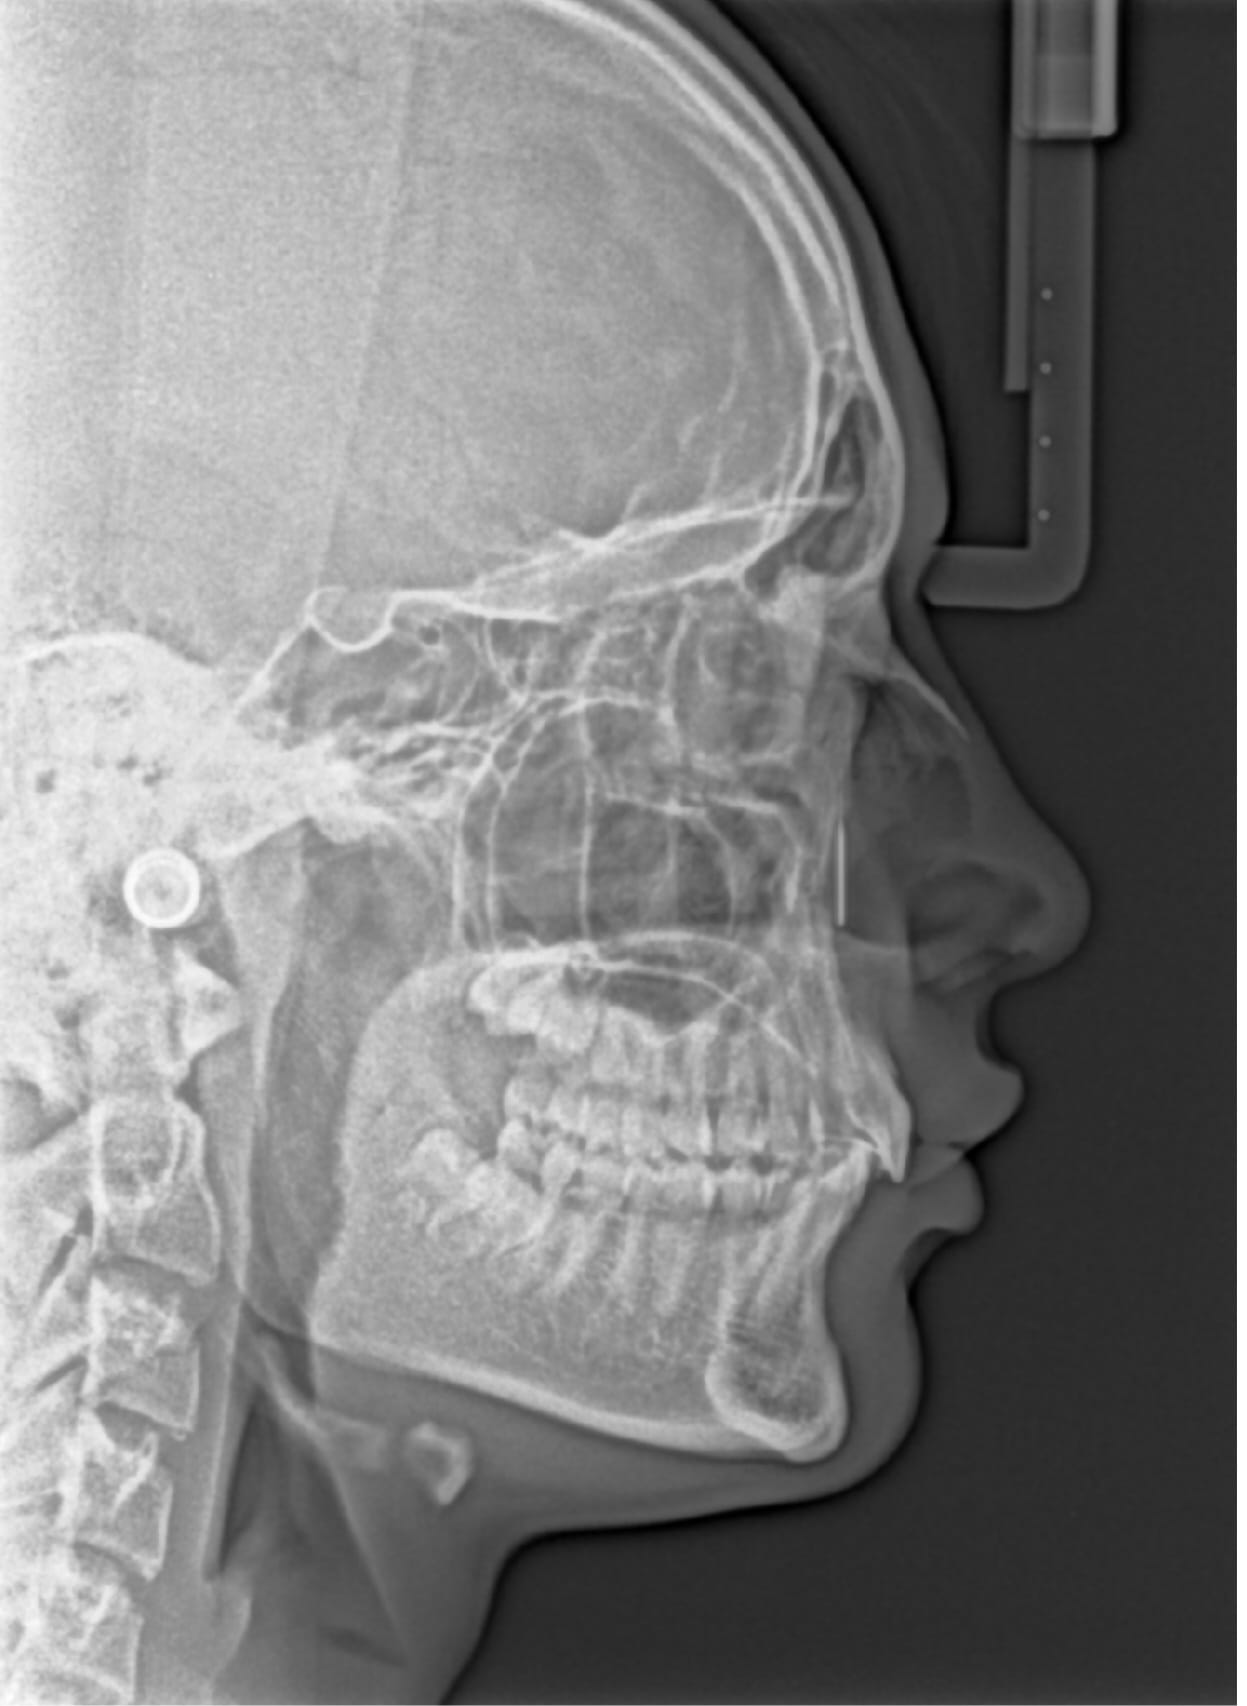

I already know I'm really recessed, so I'm hoping for either some surgery recommendations (something aggressive) as well as surgeons - In mind I'd like a Le Fort 2, BSSO and Genioplasty, and I seriously hope a Le Fort 2 is in the possible range - money isn't an issue, because I'll be making it anyway.

Since that ceph, I've had marpe done (no idea how much width I gained), and am willing to softmaxx and hardmaxx but I want to restrict hardmaxxes to bone-moving surgeries only, and exogenous hormones (might not be considered a hardmaxx but still willing to do)

curretly 17, turn 18 in October